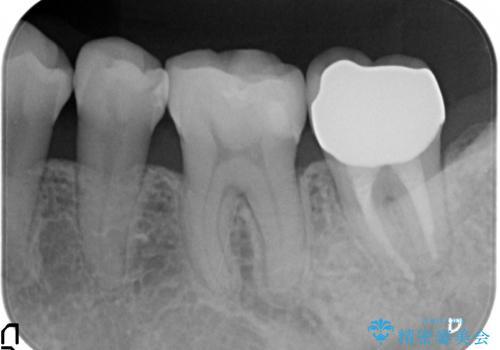

オールセラミッククラウン 痛みが引かない歯の治療

- 他院にて根管治療を行っていたが、痛みが引かないため当院での診療を希望された方の症例です。

改めて再根管治療を行い、症状の緩解を確認後、オールセラミッククラウンによる補綴を行いました。

- オールセラミッククラウン…¥100,000、ファイバーコア…¥20,000費用は治療当時の料金となります

今回用いたオールセラミッククラウンはジルコニアフレームという白い素材の上にセラミックを盛っているため、審美性が非常に高いのが特徴です。

また、ジルコニアは人工ダイヤモンドの材料にも使われているほど高い強度を持っており、そのためオールセラミッククラウンは審美性だけでなく、奥歯やブリッジの補綴も可能とするクラウンです。